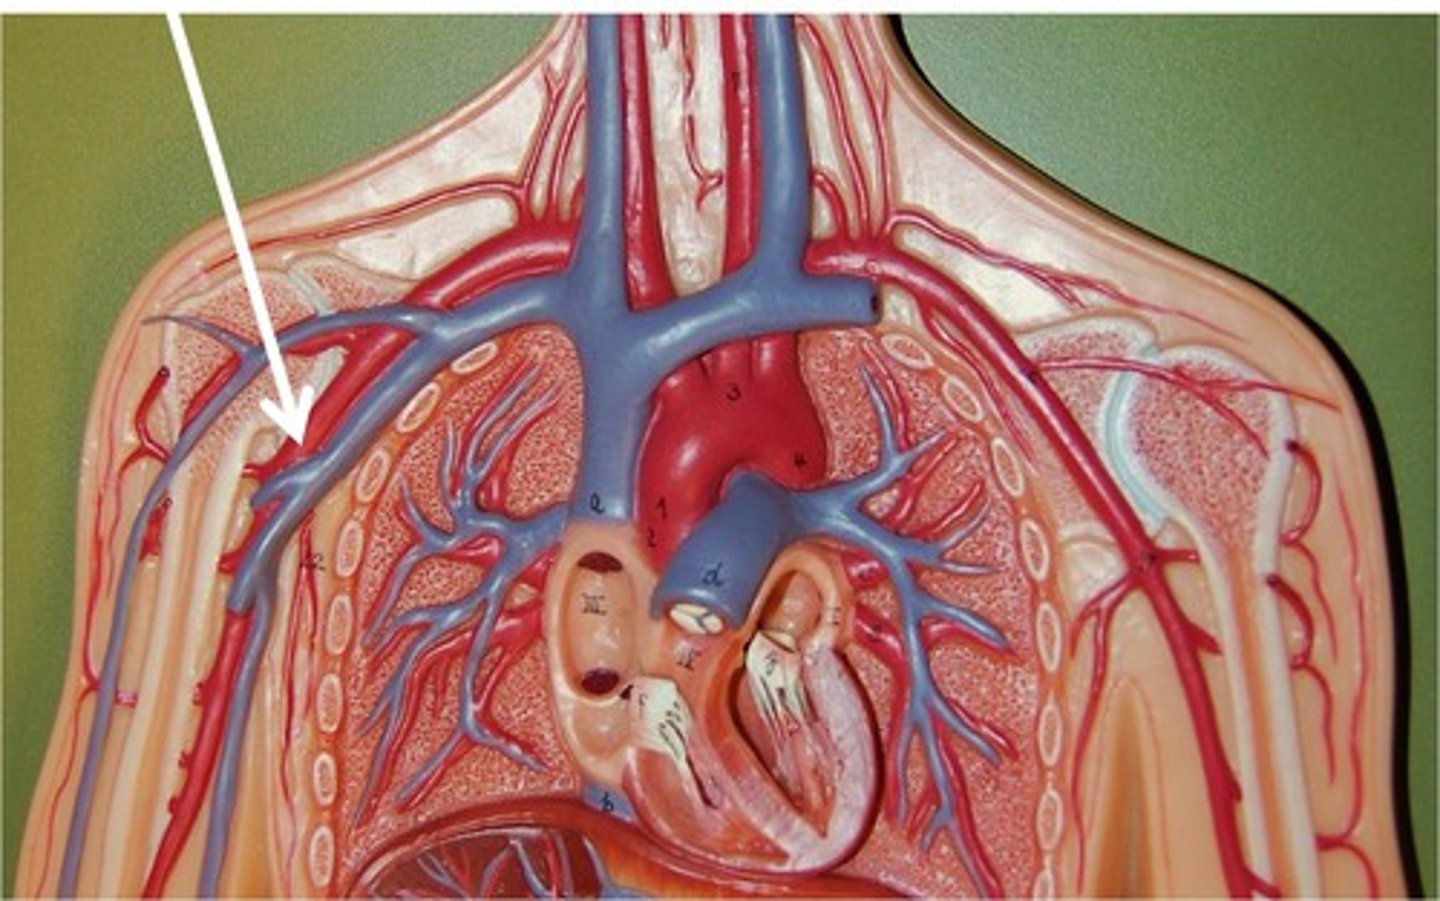

axillary vein

brachial vein

cephalic vein

radial vein

ulnar vein

subclavian vein

brachiocephalic vein